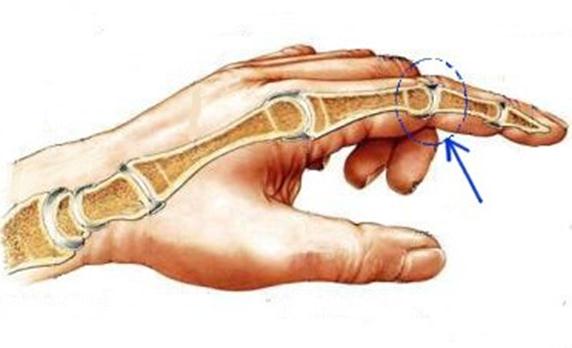

S: Стрелка указывает на art....

S: Стрелка указывает на art....

S: Стрелка указывает на art....

S: Стрелка указывает на art....